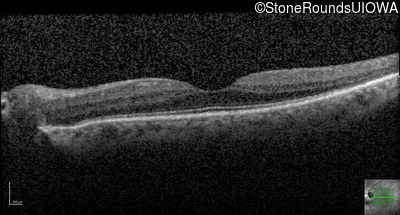

Optical Coherence Tomography - Right - 20/16 -1

Exemplar / OCT Stack